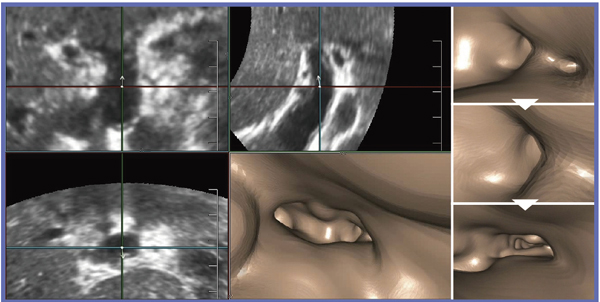

●症例3:膵管内乳頭粘液性腫瘍(IPMN,70歳代,女性)

IPMN(膵管内乳頭粘液性腫瘍)の症例である。主膵管は体部から尾部にかけて拡張しており,Bモード画像でも主膵管の尾側端に複数の乳頭状の腫瘤を確認でき,主膵管型IPMMと診断した(図6c↓)。短軸方向でみると内腔面が狭くなり,乳頭状の腫瘍が内腔に張り出していることがわかる(図6d↓)。

図6 症例3:膵管内乳頭粘液性腫瘍(IPMN)のBモード画像

MPD:主膵管

Cavity(USCP)では,主膵管拡張の状態を表現することができる。しかしながら,当然,内腔面の変化はわからない(図7)。膵頭部から膵尾部方向にFly Thruすると,内腔に突出した複数の乳頭状腫瘤を認識できた(図8)。

図7 症例3:IPMNの主膵管(MPD)のCavity(USCP)画像

図8 症例3:IPMNのFly Thru画像(膵頭部から膵尾部方向へ)